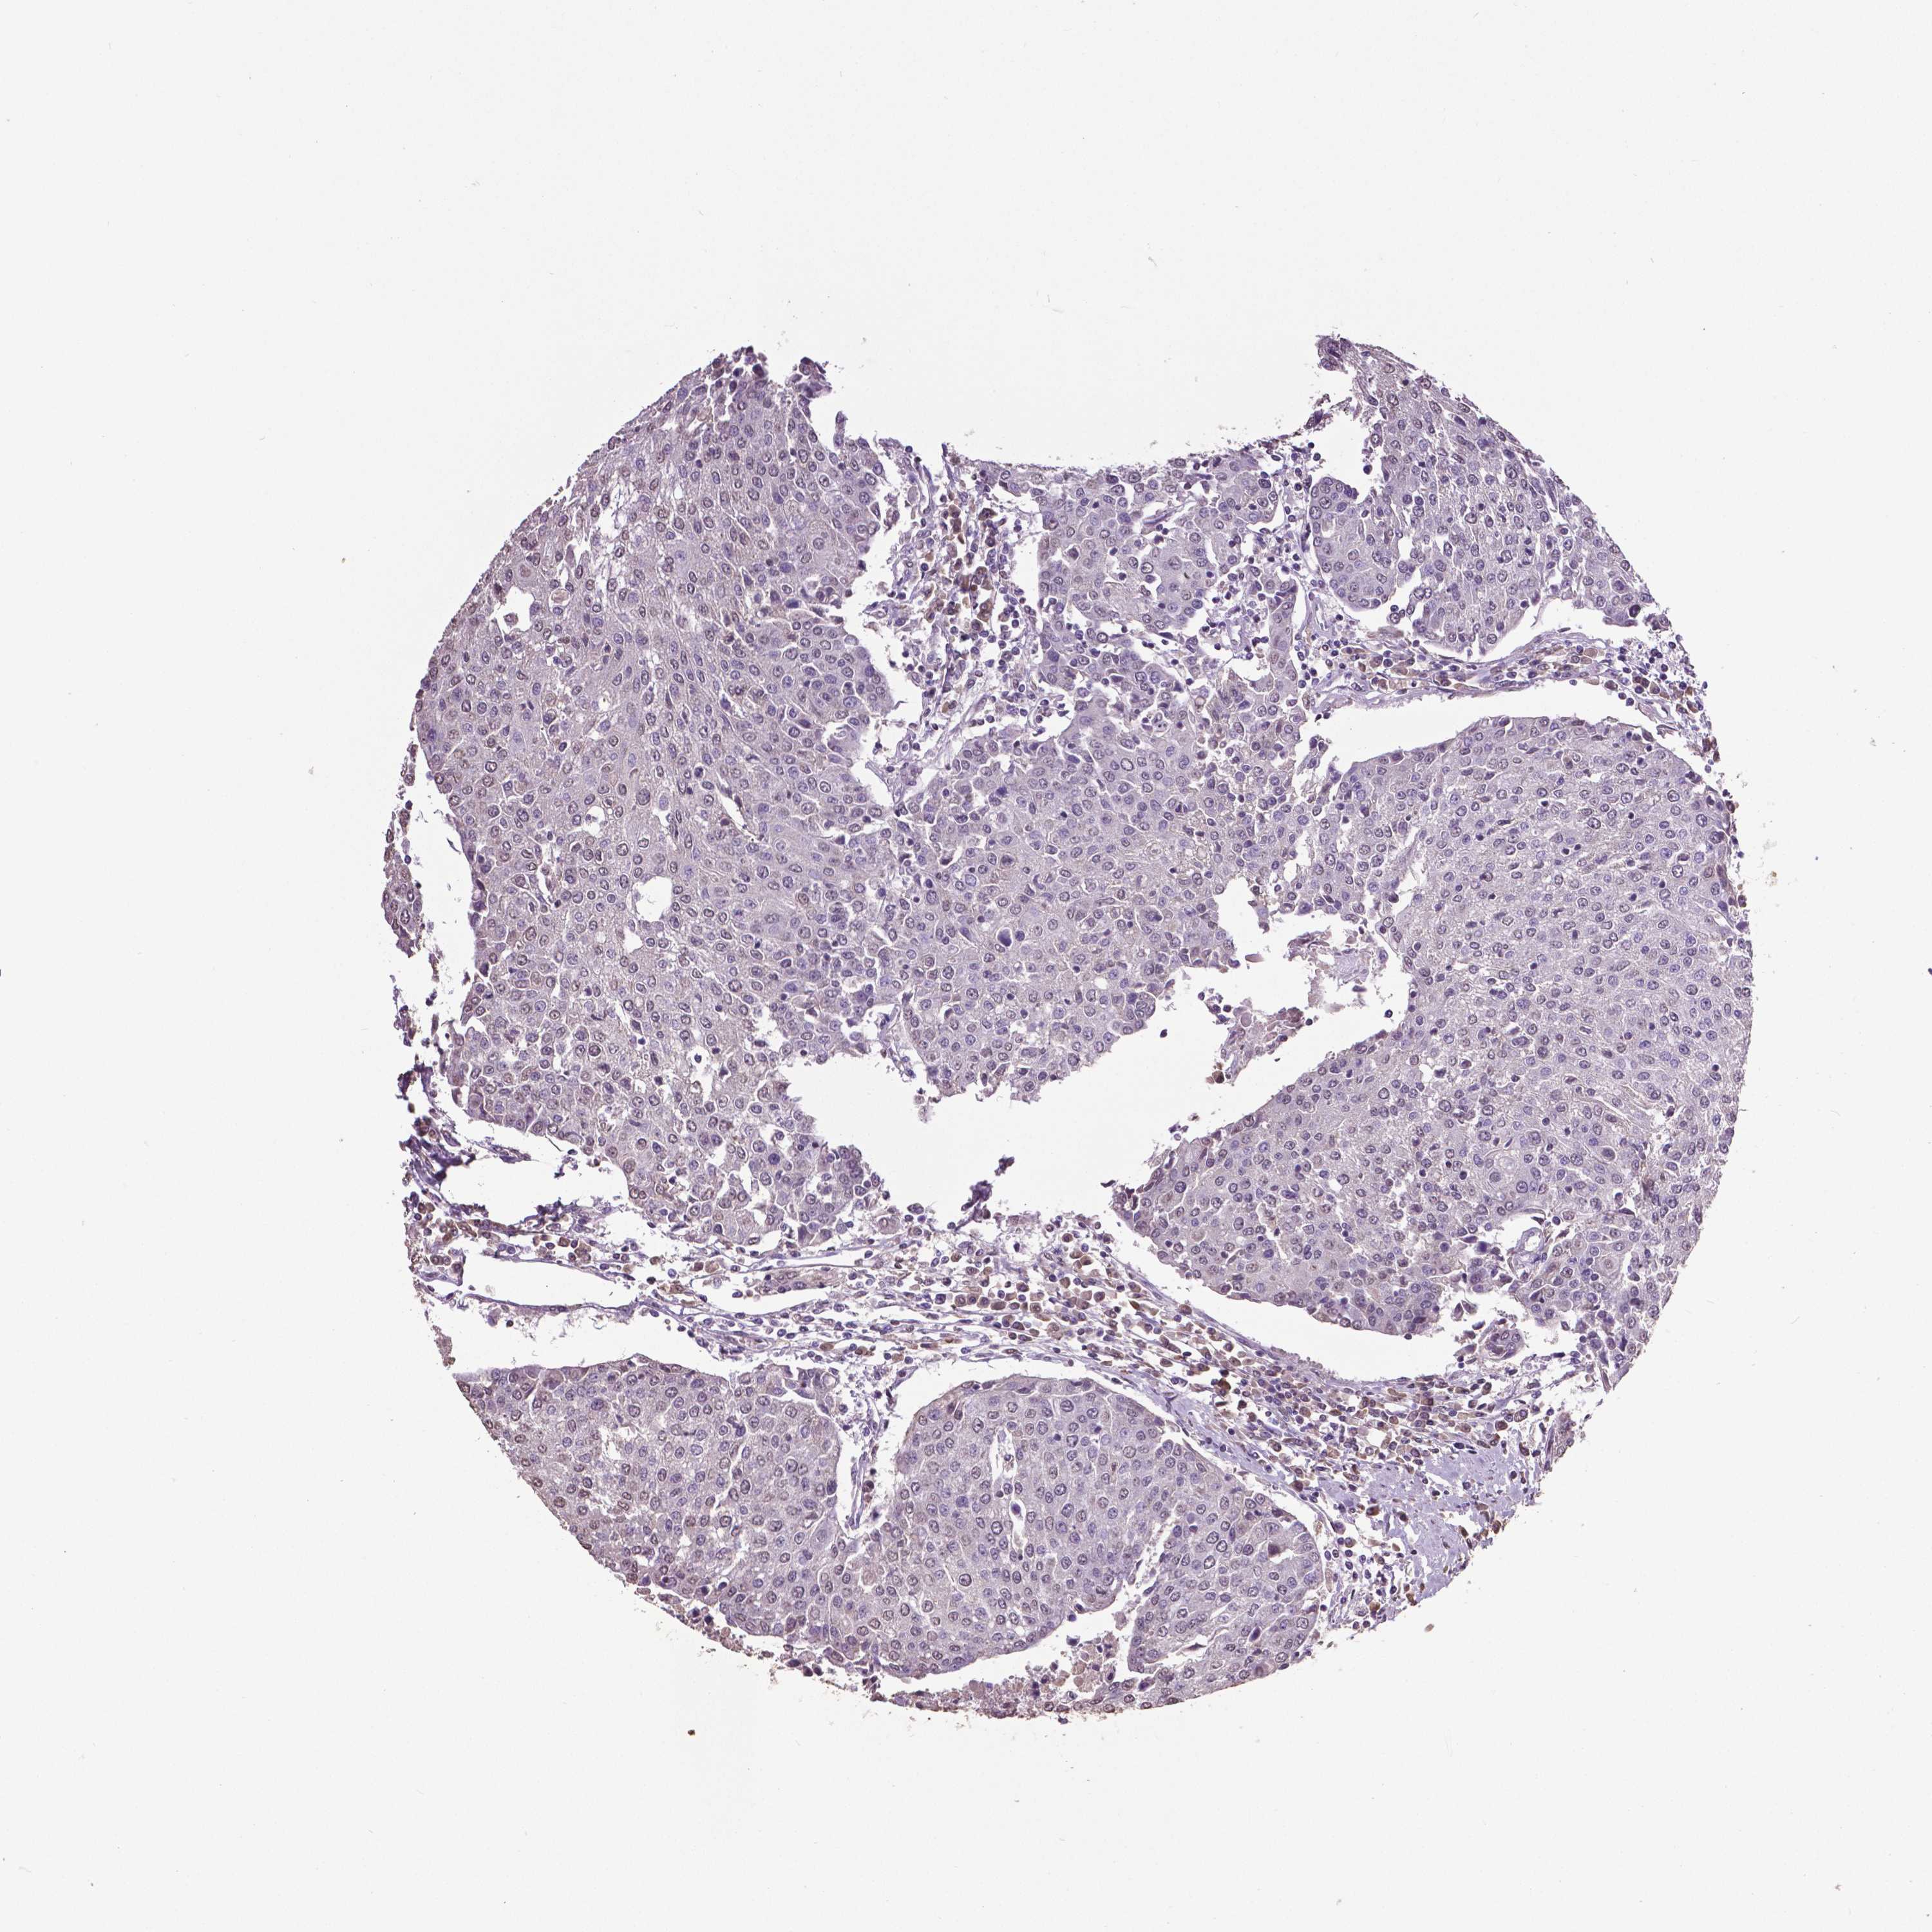

UROTHELIAL CANCER - Protein expressioni

A mouse-over function shows sample information and annotation data. Click on an image to view it in a full screen mode. Samples can be filtered based on level of antibody staining by selecting one or several of the following categories: high, medium, low and not detected. The assay and annotation is described here.

Antibody stainingi

Antibody staining in the annotated cell types in the current human tissue is reported as not detected, low, medium, or high, based on conventional immunohistochemistry profiling in selected tissues. This score is based on the combination of the staining intensity and fraction of stained cells.

Each image is clickable and will lead to virtual microscopy that enables deeper exploration of all samples and also displays staining intensity scores, fraction scores and subcellular localization as well as patient and tissue information for each sample.

Antibody HPA059006

Antibody CAB025416

Urothelial carcinoma, High grade

Urothelial carcinoma, NOS

Urothelial carcinoma, Low grade